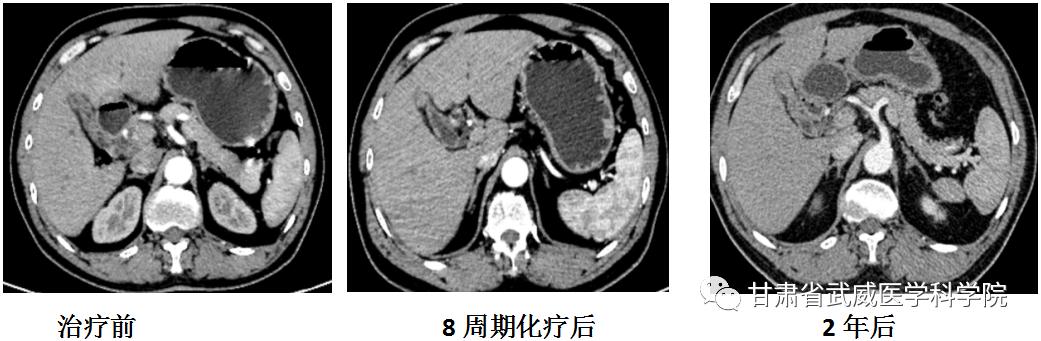

2021年3月赵某因“腹泻及腹痛”就诊于化疗科,腹部CT提示:胆囊窝占位,考虑胆囊癌,侵及邻近肝实质、胃窦部;胃左动脉受累;肝内多发病灶,肝门部肿大淋巴结,考虑转移;在超声引导下行经皮肝肿物穿刺活检术,肝脏肿物穿刺病理结果示:送检肝组织及增生的纤维组织,纤维组织中见低分化腺癌组织浸润,结合免疫组化检测结果,多考虑来自胆道。王慧娟主任医师详细分析了赵某的病情,与患者及家属充分沟通后,于2021年3月-2021年7月行一线8周期姑息性化疗联合免疫检查点*制剂抑**治疗2年。期间定期复查提示病变先缩小随后稳定,患者症状较前明显缓解。

直至目前,患者已完成免疫治疗2年,患者病情依然稳定,已远超出初诊时的预计生存期,我院化疗科会继续随访此患者。预防任何癌症,都离不开健康的生活方式。不吸烟、不超重,健康饮食(少吃碳水化合物,均衡营养)、规律运动,让我们的身体保持一个良好的健康状态。